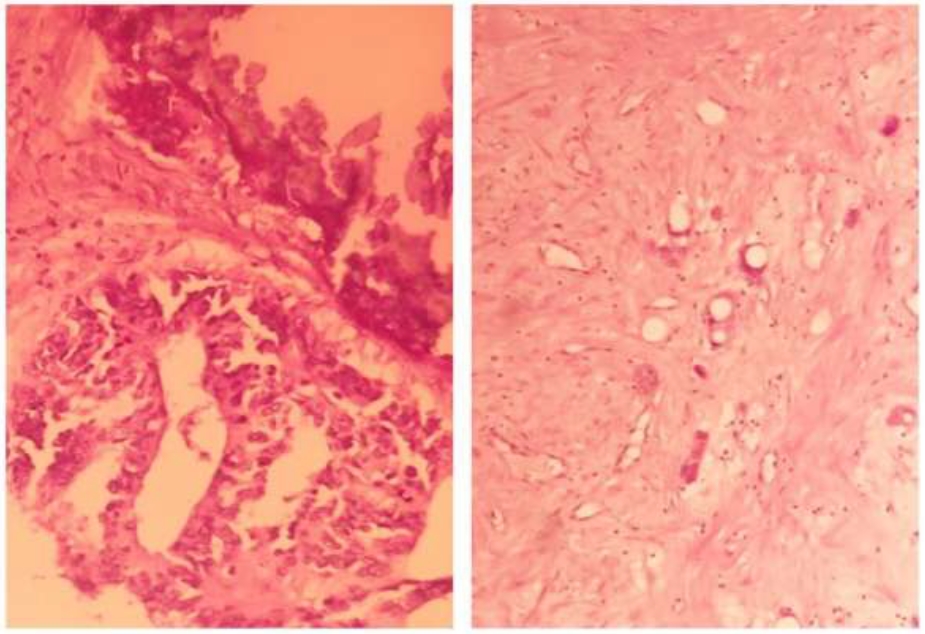

В первой группе, где резекционное вмешательство проводилось через 7 дней после регионарной химиотерапии лечебный патоморфоз, наблюдался у 13/15 больных. У 11/13 больных зафиксирована 2 степень лечебного патоморфоза, которая заключалась в наличии полей фиброза и скудной воспалительной инфильтрации (рис. 5) на фоне сохраненной опухолевой ткани.

У 2/15 больных лекарственного патоморфоза не зафиксировано. У 2/13 больных зафиксирована 1 степень лечебного патоморфоза, который заключался у одного больного – в виде фиброза отдельно лежащих желез и кальцинатов (рис. 6), у другого больного – в виде миксоматоза, рассеянной воспалительной инфильтрации и очагах некроза.

Рис. 5. Метастаз аденокарциномы кишечного типа с наличием полей фиброза (А) и воспалительной инфильтрацией (Б). Вторая степень лечебного патоморфоза (окраска: гематоксилин и эозин, х 400)

Рис. 6. Метастаз аденокарциномы кишечного типа. Умеренный лечебный патоморфоз (grade 1). Фиброз отдельно лежащих желез и появление кальцинатов. (окраска: гематоксилин и эозин, х 400)